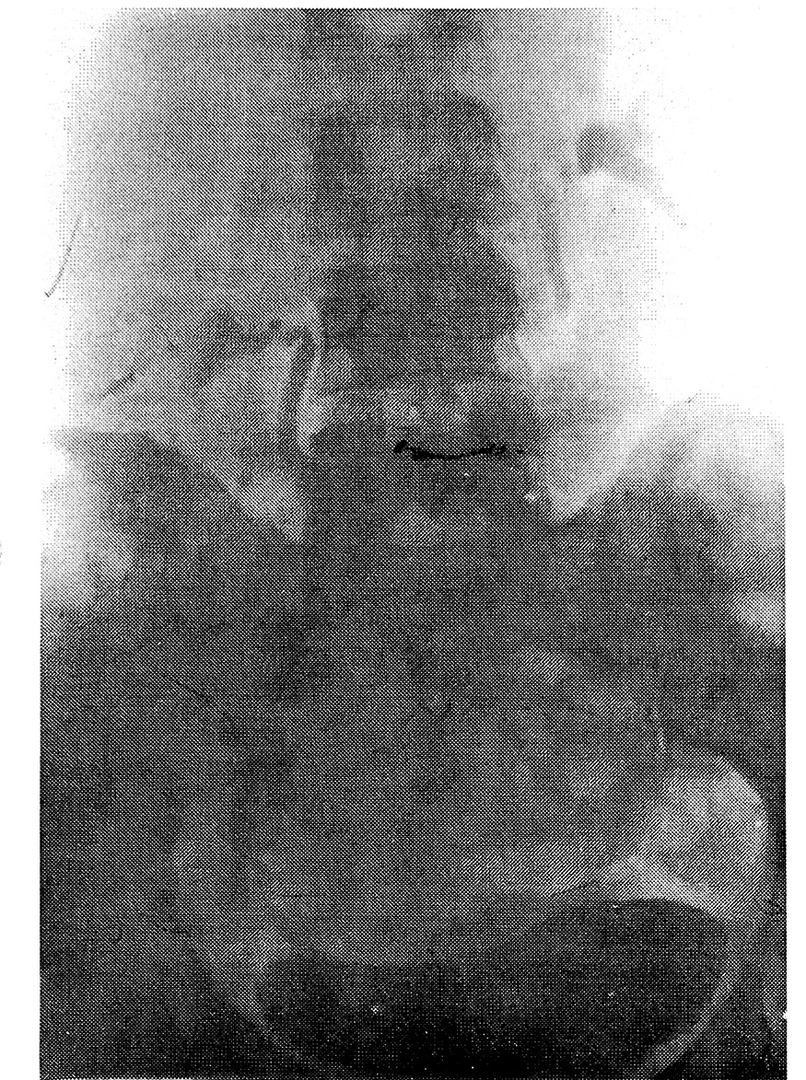

Рис. 2. Внутривенная экскреторная урография больной Н., 34 лет, в клиностазе: двусторонний нефроптоз, гидронефротическая трансформация, коленообразные перегибы мочеточников. Нефроптоз III степени в ортостазе

Кроме того, мы вычисляли относительное сужение и удлинение почечной артерии (рис.3). В норме ПУУ равен 110— 130°. В ортостазе он уменьшается на 10— 20°. При нефроптозе он становится острым в зависимости от степени смещения. Но величина этого угла не всегда соответствует степени смещения почки: при небольшом смещении вниз возможна более выраженная ее ротация, и наоборот. По разнице ПУУ на ВЭУ в клиностазе и ортостазе можно вычислить поворот почки вокруг продольной оси. Для вычисления поворота почки вокруг поперечной оси и определения степени нефроптоза, по данным ВЭУ, определяли длинник почки в положении больного лежа и стоя. По разнице длинни- ков почек вычисляли искомый угол по формуле (1/2R : 1/2 R1) = cosа. Относительное сужение почечной артерии при нефроптозе, по данным ВЭУ, определяют следующим образом: на урограмме в клиностазе по левому краю остистых отростков позвоночника проводят вертикальную линию (при нефроптозе справа — соответствующую правому краю аорты). Место отхождения почечной артерии соответствует пересечению горизонтали от шейки верхней малой чашечки к краю аорты, h — длина почечной артерии в клиностазе и h1 — в ортостазе. Сужение почечной артерии вычисляли по формуле: V= Пr2h (лежа); Ѵ= Пг21h1; r2h= г1 2h1. Относительное сужение почечной артерии r1=√h/h1 х 100г, где (в %) г/г = √h/h. В настоящее время нарушение кровообращения, диаметры почечной артерии и вены можно определить используя УЗИ с ЦДК.При патологической подвижности почка не только смещается в каудальном направлении, но и поворачивается вокруг продольной и фронтальной (поперечной) осей. Как известно, в норме в ортостазе ротация почки не превышает 19°. Формальная степень смещения не полностью отражает характер и тяжесть нарушения механизма фиксации почек. Важно установить ортостатические нарушения функции почек (нарушение кровообращения, уродинамики, функциональные расстройства почек). Ротацию почек в ортостазе мы определяли по А.И. Радавичус, Ч.А. Синкевичус [4] (рис.1, 2).